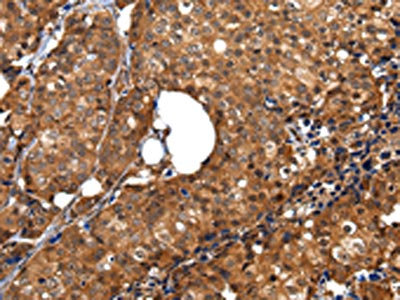

The image on the left is immunohistochemistry of paraffin-embedded Human breast cancer tissue using CSB-PA257697(ZBTB2 Antibody) at dilution 1/40, on the right is treated with synthetic peptide. (Original magnification: ×200)

The image on the left is immunohistochemistry of paraffin-embedded Human esophagus cancer tissue using CSB-PA257697(ZBTB2 Antibody) at dilution 1/40, on the right is treated with synthetic peptide. (Original magnification: ×200)